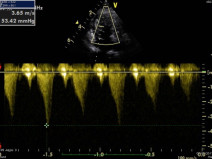

- décrire la présentation clinique des principaux cancers rencontrés dans l’espèce féline et les outils (biologiques, imagerie) indispensables de la démarche diagnostique ;